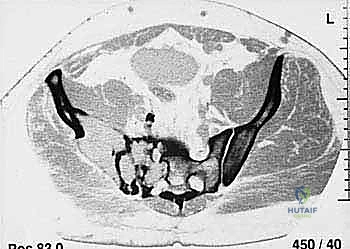

* CT with Intravenous Contrast and 3D Reconstruction (FIG 3): This is our workhorse for assessing bone involvement, destruction, and the critical relationship between the tumor and major pelvic blood vessels. It reveals any distortion of the pelvic anatomy and guides resectability. Figure 3A clearly shows extensive bone destruction and tumor extension into the pelvis and gluteal region. Figure 3C highlights an extensive tumor on the medial aspect of the ilium with destruction of the inner table.